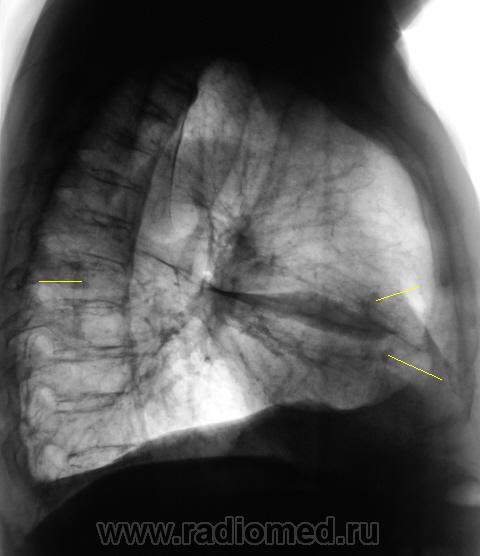

Флюорограмму расшифровывал врач того учреждения, откуда флюорограф, ну и рекомендацию "что сделать" - от туда. Но с учетом наличия синдрома "затемнения вне анатомических границ", конечно, лаборанты сделали и боковую, а уже только после этого пригласили "нашего" врача-рентгенолога "для принятия решения".

И фрагмент с увеличением. Что посоветуете tatyana ?

Конечно, я понимаю, что должна быть проведена д/д между "осумковнным выпотом" и "швартообразующим процессом". Что посоветуете?

Повезло с лаборантами!.. Поскольку, помимо междолевого ограниченого плеврита, мне мерещатся еще очаги в легком, посоветую КТ

Я пока, это никак не трактую. Случай сегодняшний, думаю. Может коллеги, чего подскажут. Вот и последний срез. Подумываю, что в наличии и "базальный" выпот.